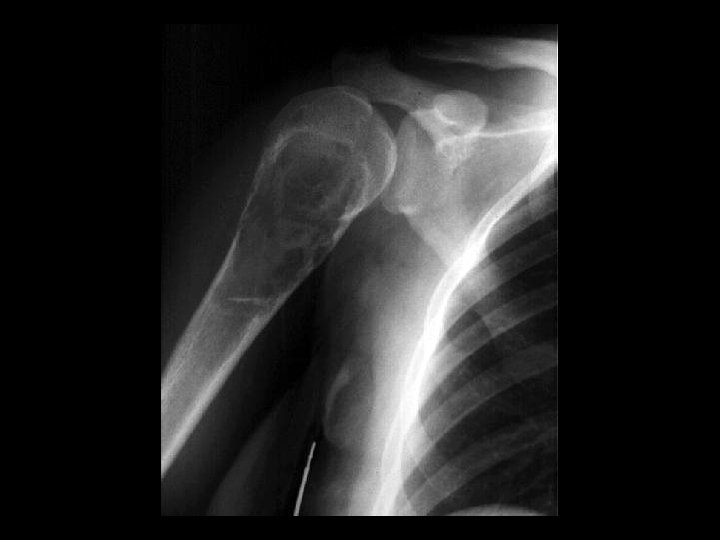

Anterior Shoulder Dislocation

Inferior shoulder dislocation • Findings: – Inferior dislocation of humeral head and a deep cleft in the superior portion • ddx: – Anterior dislocation